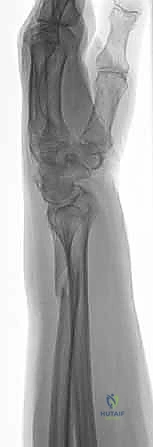

1. الأشعة السينية (X-rays): بوضعيات متعددة (أمامية خلفية، وجانبية دقيقة). الوضعية الجانبية الحقيقية (True Lateral) حاسمة لاكتشاف أي خلع جزئي في المفصل (DRUJ).

2. الأشعة المقطعية ثلاثية الأبعاد (3D CT Scan): تُستخدم في الكسور المفتتة أو كسور رأس الزند المفصلية المعقدة، حيث تعطي خريطة دقيقة للجراح قبل الدخول لغرفة العمليات.